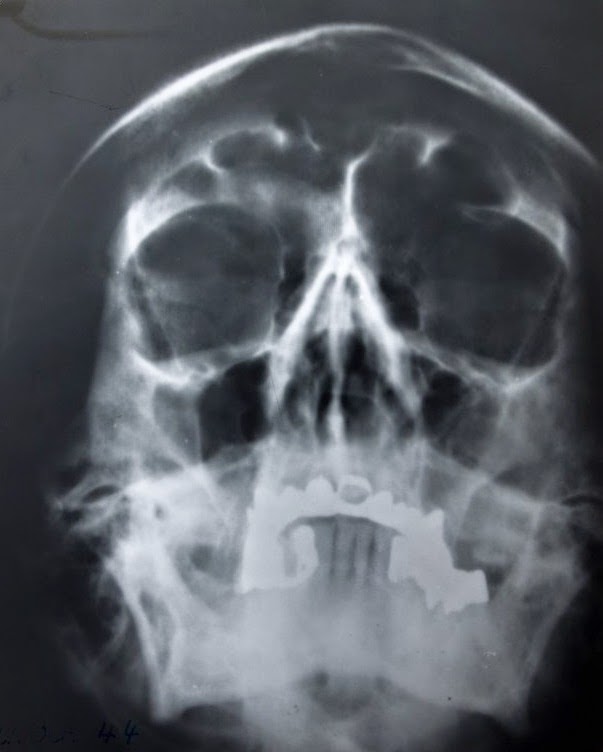

O estado de saúde de Hitler naqueles dias era bastante precario. Desde o atentado que sofrera em 20 de junho de 1944, seu estado físico estava em constante degradação. O agravamento do Mal de Parkinson bem como a enorme quantidade de remédios que tomava diariamente - chegava a tomar vinte comprimidos diferentes todas as manhãs - podem ter contribuído para o agravamento de seu estado físico e mental. O seu medico particular, Dr. Morel, lhe receitava uma serie de remédios que na maioria das vezes não tinha nenhum efeito benéfico para sua saúde. Alguns continham uma pequena porcentagem de estricnina, além de pílulas para gases estomacais, injeções diárias de estimulante físico que suprimiam o cansaço, injeções hormonais e um colírio a base de cocaína (1%) que Hitler aplicava nos olhos todas as manhãs. Todas as noites ele precisava de uma injeção de sedativo para conseguir dormir. O escritor alemão Joachim Fest, autor da uma respeitada biografia de Hitler, descreveu o seu estado de saúde nos últimos dias de abril de 1945:

“Sua pele que já era viscosa havia anos, as feições ultimamente intumescidas, e as bolsas escuras e inchadas sob os olhos. Bastante curvado e com movimentos estranhamente oscilantes, ele andava muito próximo as paredes do bunker, como se procurasse apoio. Seu uniforme ate então impecável, apresentava manchas de restos de comida; nos cantos dos lábios havia migalhas de bolo; e sempre que segurava os óculos com a mão esquerda, ao fazer um relato da situação, eles batiam de leve no tampo da mesa. Fisicamente, seu aspecto era horrível. Cansada e pesadamente jogando a parte superior do corpo para frente e arrastando as pernas atrás de si, ele se movimentava dos seus aposentos para a sala de conferencias no bunker. Faltava-lhe a sensação de equilíbrio; quando era parado no curto percurso (20 a 30 metros) tinha de se sentar em um dos bancos dispostos nas paredes dos corredores com esse propósito ou se segurar no interlocutor. Os olhos estavam injetados, embora todos os documentos a ele destinados, tivessem de ser redigidos na “maquina de escrever do fuhrer” cujas letras tinham três vezes o tamanho das letras normais, ele precisava de lentes grossas para lê-los.”